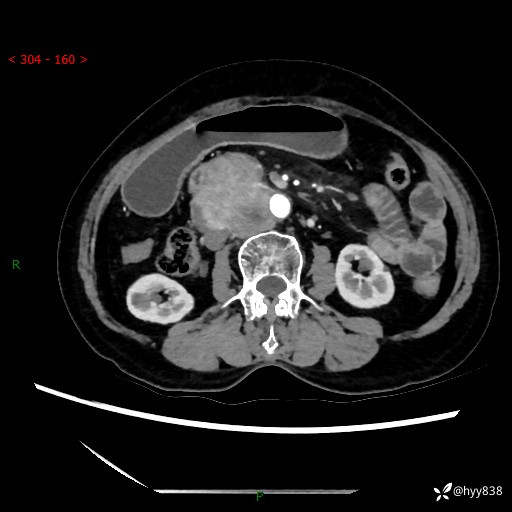

71岁/女,腹痛1月余。腹膜后肿物,间质瘤 VS 副节瘤 VS 平滑肌肉瘤---(有结果)

【患者信息】:71岁/女

【主诉】:腹痛1月余

【检查】:腹部CT增强扫描(外院CT平扫)